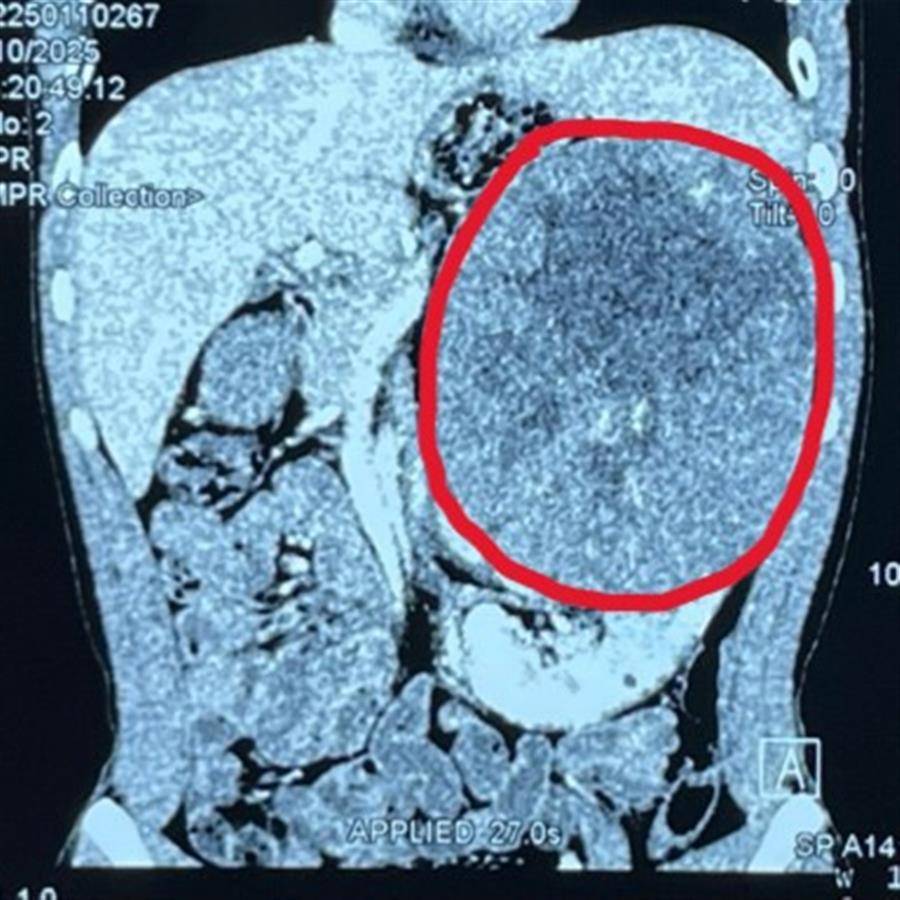

1月下旬,2位患者几乎同时到该院泌尿外I科求助。一位是年仅18岁的小伙小张,因身体不适在湖北某县医院检查时,查出左肾有一个17.5厘米X14.3厘米X16.8厘米的巨大实质性占位性肿块。另一位是47岁的陶姓女士,她在体检时发现左肾巨大实质性占位性病变,并伴随腔静脉癌栓形成,穿刺活检病理证实还有上皮样血管及脂肪瘤,进一步完善检查发现癌栓已进入下腔静脉,并达到MayoII级。

泌尿外I科主任陈志远教授带领团队评判病情后认为,2位患者的肾脏肿瘤体积已占据了大半腹腔,压迫邻近重要器官,随时可能危及生命。